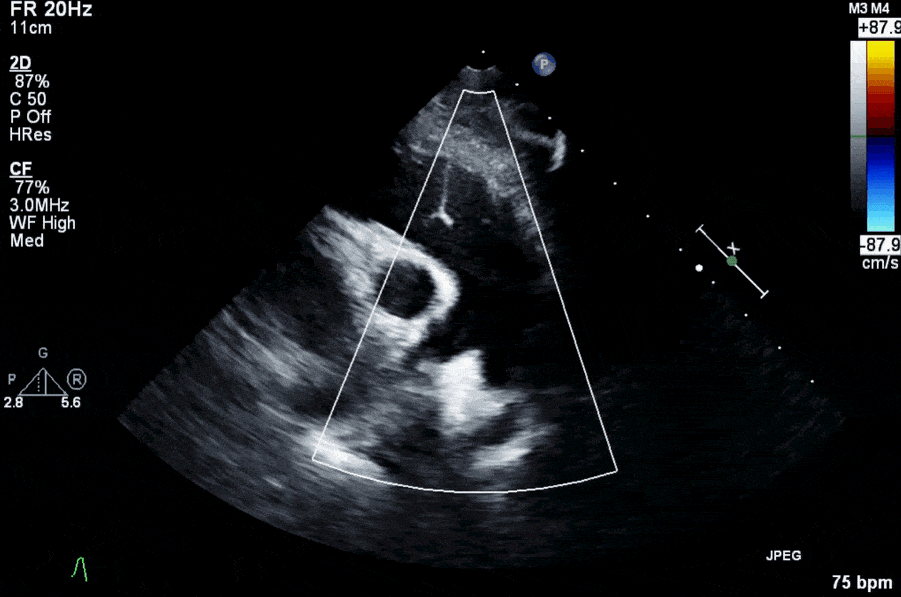

- ECG, Chest Xray, Echo